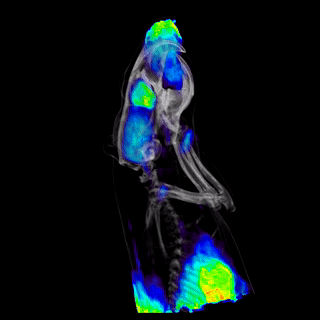

CASE 6: Prostate investigation using [18F]NaF

• Courtesy of: P. Laquerriere, D.Brasse, IPHC CNRS, Strasbourg

Research objective:The calcification (size < 1 mm) in the prostate close to the bladder could be clearly observed using [18F]NaF radiolabelled molecule. The identification of the mouse prostate is a challenging task using in vivo imaging due to its size and shape. Images were made using the IRIS PET system (Inviscan). The system demonstrates high sensitivity and excellent spatial resolution.

Animal model:Mouse, 38.7g, spontaneous model of prostate cancer developed by D. Metzger (IGBMC, Strasbourg, France)

Acquisition protocol:10 min acquisition time, 1 bed position

Processing and reconstruction protocol:3D-OSEM, 0.855 x 0.855 x 0.855 voxel size

Biomarker or contrast agent:Mice were injected with 7.6 MBq [18F]NaF.